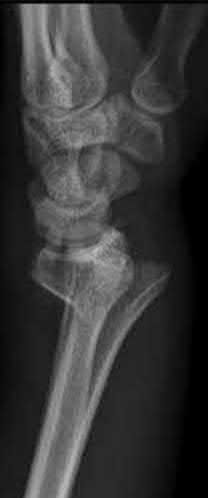

Question 6:

A 22-year-old male falls onto an outstretched hand and sustains a displaced fracture through the proximal pole of the scaphoid. Avascular necrosis of the proximal pole is highly likely due to the disruption of its primary vascular supply. Which vessel provides this critical retrograde perfusion?

Correct Answer: Dorsal carpal branch of the radial artery

Explanation:

The primary blood supply to the scaphoid is from the dorsal carpal branch of the radial artery, which enters the dorsal ridge of the scaphoid at the waist and courses proximally. This retrograde blood flow makes proximal pole fractures highly susceptible to avascular necrosis and nonunion. The superficial palmar branch provides a minor supply (about 20%) to the distal pole.